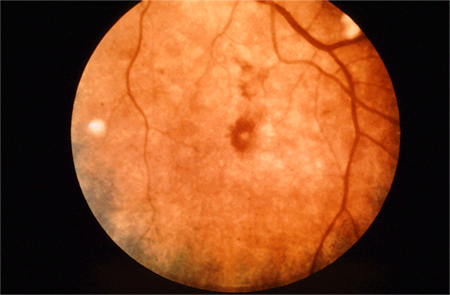

Infective endocarditis: infection involving the endocardial surface of the heart, including the valvular structures, chordae tendinae, site of septal defects, or the mural endocardium. Rare skin manifestations are Janeway lesions (painless maculopapular lesions on palms and soles) and Osler nodes (painful nodules on tips of fingers). Children with congenital heart disease have an increased risk of infective endocarditis.[51] Bacterial aetiologies include Staphylococcus aureus, Enterococcus, Streptococcus bovis, Streptococcus viridans, and HACEK (Haemophilus species, Actinobacillus actinomycetemcomitans, Cardiobacterium hominis, Eikenella corrodens, Kingella species) organisms.[51] Fungal endocarditis is unusual in children, but can be seen in the setting of indwelling central catheters.[52] Presenting symptoms may include fever, malaise, fatigue, night sweats, or heart palpitations. Janeway lesions, Osler nodes, and Roth spots (hemorrhagic retinal lesions) are more common in subacute endocarditis.[52][Figure caption and citation for the preceding image starts]: Janeway lesionsFrom the collection of Sanjay Sharma, St George’s University of London, UK; used with permission [Citation ends].

[Figure caption and citation for the preceding image starts]: Roth spotsFrom the collection of Sanjay Sharma, St George’s University of London, UK; used with permission [Citation ends].